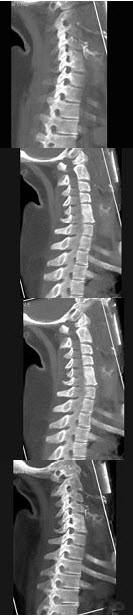

193、单项选择题

男,35岁,反复颈部不适20余年,结合图像,最可能的诊断是()

A.颈椎椎体融合

B.颈椎结核

C.颈椎退行性变

D.颈椎压缩性骨折

E.颈椎骨转移瘤